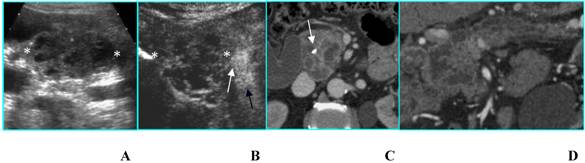

Double benign intraductal papillary mucinous tumor in an asymptomatic 72-year-old woman. A. B-mode US shows two simple cysts (arrows) located in the head of the pancreas. B. CEUS confirms the presence of two simple cysts without septa or mural nodules (arrows). C and D. MR on axial T2-weighted image (C) confirms the unilocular aspect of the cysts (arrows) and on coronal T2-weighted image (D) well demonstrates the communication of the greater cyst with the pancreatic duct (arrowhead).

Benign intraductal papillary mucinous tumor in an asymptomatic 81-year-old woman. A. B-mode US shows a huge multilocular cyst (calipers) with compartments > 2 cm in diameter located in the head of the pancreas. B. CEUS better shows thin septa and absence of papillary projections in the lesion (calipers). Portal vein (arrow) is filled with contrast agent. C and D. MDCT on axial image (C) confirms a macrocystic lesion with thin septa; on curved reformatted image (D) the communication with the pancreatic duct is demonstrated.

Malignant intraductal papillary mucinous tumor in a 80-year-old man who presented with obstructive jaundice. A. B-mode US shows a multilocular cystic lesion with mural nodules (calipers) located in the head of the pancreas. B. CEUS well depicts the vascularized septa and nodules in the lesion (calipers). Superior mesenteric artery (black arrow) and superior mesenteric vein (white arrow) are filled with contrast agent. C and D. MDCT on axial image (C) shows a multilocular lesion with a solid component; a stent is inserted in the common bile duct (arrow); on the curved reformatted image (D) the communication of the tumor with the pancreatic duct is demonstrated.

Likewise, when two or more unilocular cysts are present, the differential diagnosis – restricted between pseudocysts and IPMTs [12] - cannot be made by CEUS and the resort to CT or MR is mandatory (Fig. 7).

c) Macrocystic lesions include multilocular cysts with fewer compartments than SMAs; besides, the compartments (> 2 cm) are larger [12]; this category includes MCN and IPMT. A thick wall, thick septa and mural or septa calcifications are the most important findings associated with malignancy [12,14]. In these cases, although CEUS permits a better visualization of wall and septa [15], it does not give a significative diagnostic gain in comparison with B-mode US (Fig. 8).

d) Cysts with a solid component at B-mode US may be either unilocular or multilocular; true cystic tumors (MCN and IPMT) as well as solid tumors with a cystic component or cystic degeneration – primary or metastatic – are included in this category. All tumors of this group are either malignant or have a high malignant potential [12]; in these cases too CEUS does not offer a meaningful diagnostic contribution (Fig. 9).